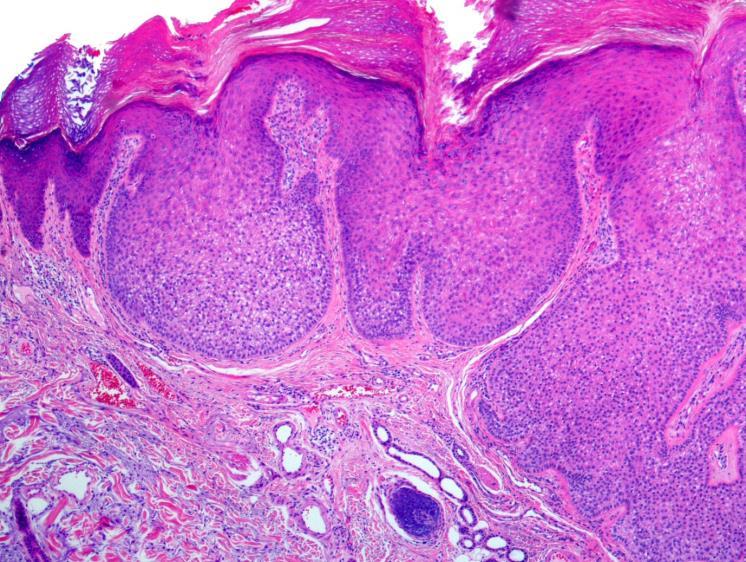

• Trichoblastoma and trichoepithlioma

• Dual differentiation towards follicular germinative epithelium and follicular papillae

• Head and neck

• Can be associated with naevus sebaceous and syndromes (BSS)

• Well defined, nodular nested proliferation of basaloid cells with follicular differentiation

• Palisading of cells

• Papillary mesenchymal bodies

• No cytonuclear atypia

• No retraction – dd with BCC

• Contain Merkel cells – CK20